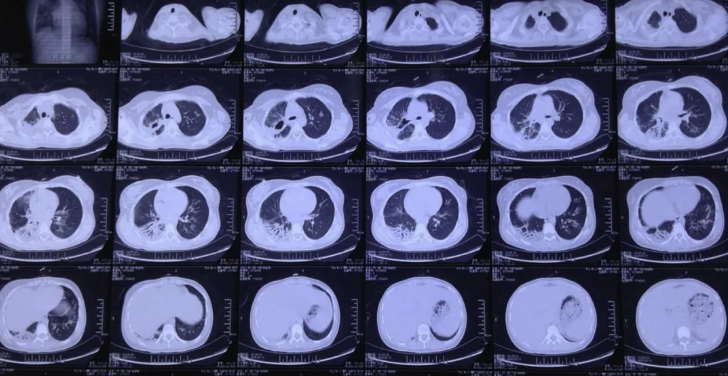

经6个月系统治疗,患者一般情况显著改善,咳嗽、气喘消失,血糖控制稳定。复查胸部CT(2018.06.09),显示肺部病变进一步吸收好转。末次支气管镜(2018.06.11)见右主支气管及上叶支气管轻度瘢痕狭窄,无坏死物及伪膜。之后随访,一般情况良好,未发生肺部感染。

图10:2018.06.09胸CT